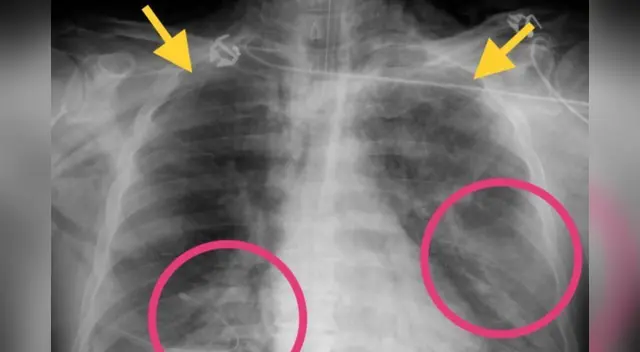

Un radiólogo de Irán, Bahman Rasuli, compartió las impactantes imágenes de una tomografía de una mujer de 30 años donde detectó neumonía severa causada por el coronavirus en los pulmones de la paciente, sin embargo, tenía un estado de salud estable y no mostraba ningún signo de la mortal pandemia, según informó la ABC.

Asimismo, las imágenes mostraron “zonas de opacidad en los pulmones” de la paciente, lo cual representa que tenía líquido en esos lugares provocados por la neumonía originada por coronavirus.

Cabe resaltar que el caso de esta mujer iraní facilita a los doctores identificar anormalidades específicas ocasionadas por el covid-19 y “establece los patrones que son similares a los encontrados en las víctimas de los brotes de SARS y SROM”, señaló el medio citado.